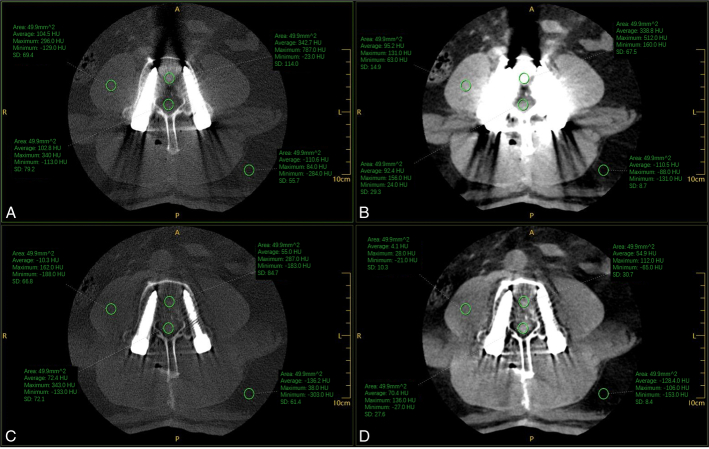

Materials and methods: A total of 57 patients who underwent lumbar spine CT examination after lumbar internal fixation from January to December 2023 in our hospital were retrospectively enrolled. The CT images were reconstructed using MAR + and non-MAR + techniques and were subdivided into MAR + and non-MAR + groups. The CT number (in Hounsfield units) and the SD noise values of the spinal canal, vertebral body, psoas major muscle, and adjacent fat were measured in the 2 groups of CT images, and the signal-to-noise ratio (SNR) and contrast-to-noise ratio (CNR) were calculated. The subjective score was evaluated by two diagnostic radiologists using a double-blind method for image quality evaluation of the MAR + group and the non-MAR + group, and the image quality was classified on a 5-point scale. The rank-sum test was utilized to compare the subjective and objective scores of the 2 groups.

Results: The SD values of the spinal canal ( Z =-4.12, P <0.01), vertebral body ( Z =-3.81, P <0.01), and psoas major muscle ( Z =-3.87, P <0.01) in the MAR + group were significantly lower than those in the non-MAR + group ( P <0.05). However, the SD values of the adjacent fat ( Z =-2.03, P =0.42) in the MAR + group, although smaller than those in the non-MAR + group, were not statistically significant. The CNR values of vertebral canal ( Z =-2.67, P =0.008) and fat ( Z =-2.60, P =0.009) were higher in the MAR + group than in the non-MAR + group, whereas the CNR values of the vertebral body ( Z =-6.74, P <0.01) in the MAR + group were smaller than those in the non-MAR + group, and the difference of all of them was statistically significant ( P <0.05). Furthermore, for both CT and SNR values, the MAR group's values were all less than those of the non-MAR group and were statistically significant ( P <0.05). The subjective scores of the measurement points were all higher in the MAR + group than in the non-MAR + group.

Conclusions: The MAR + technique has a noise reduction effect on different tissues and artifacts are significantly reduced. Although the artifacts caused by metal screws were not completely eliminated, the MAR + technique was able to reduce the interference of artifacts in the diagnosis of CT images, thus improving their diagnostic quality.